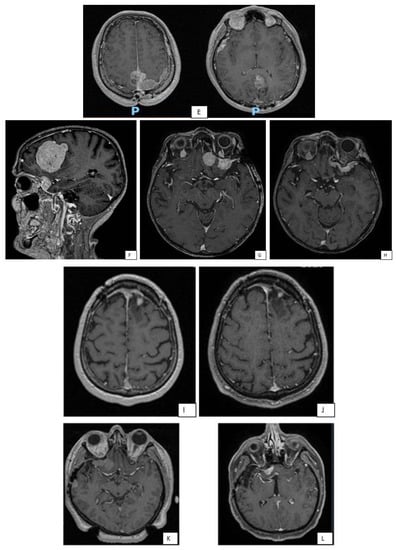

In Figure 3 some illustrative cases are reported.

Figure 3.

MRI images of some representative cases. Patient with right fronto-parietal convexity meningioma (A), subjected to GTR (Simpson I), as can be seen from the post-operative brain MRI (B). Due to the pathological features (high number of mitoses and cerebral invasion) the patient underwent adjuvant RT treatment despite surgical removal Simpson I. Good local control after two years from adjuvant RT (C). After 36 months, appearance of distal recurrence (D). MRI of a patient with multiple meningiomas (E). Patient with large left frontal meningioma, subjected to surgical removal (F), associated with two other nodules at the left sphenoidal wing, subjected to GKRS (G). Picture (H) shows good disease control 4 years after GKRS treatment. GKRS for a small recurrence of left frontal convexity meningioma (I) and relative MRI control 18 months after (J). GKRS for two nodules of right fronto-temporal meningioma (K). 15 months after radiosurgery, a new GKRS was performed on a further nodule of recurrence at the sphenoidal wing (L).